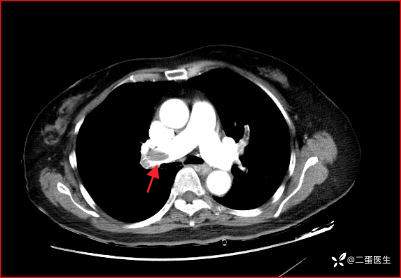

结合患者症状、体征及辅助检查结果,诊断考虑急性肺栓塞,急诊肺动脉CT血管造影(CTPA)提示右肺主干、双肺叶及段动脉内多发充盈缺损,肺栓塞诊断明确。

右肺主干、双肺叶及段动脉内多发充盈缺损